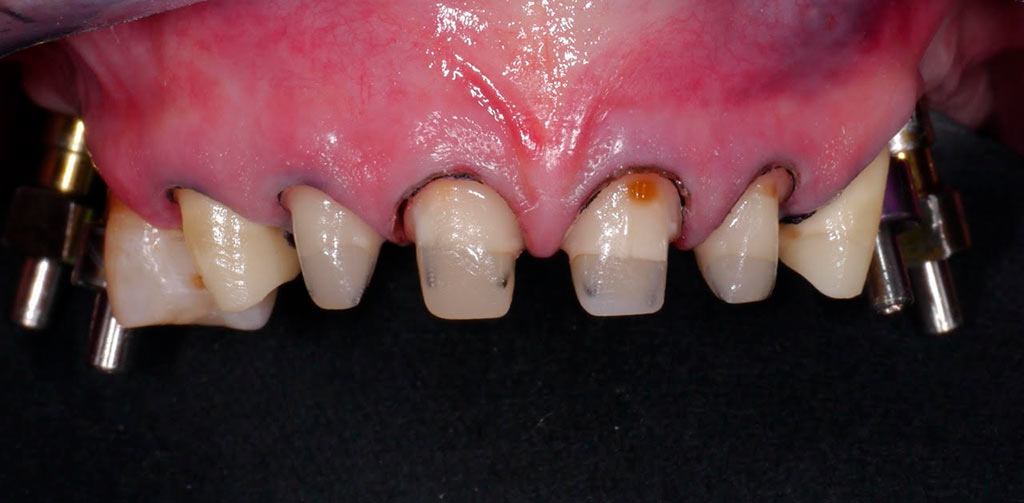

Completa inmediata,cirugía guiada, prótesis, puente de zirconio

Rehabilitacion de paciente con destrucción dental